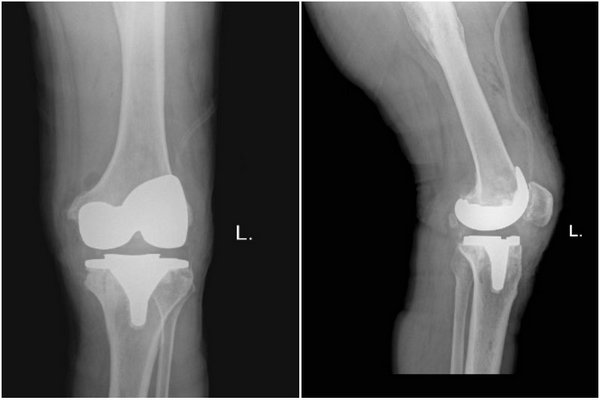

术后影像